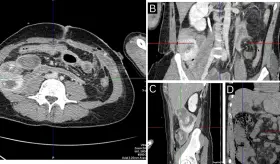

El hematoma comprimía la médula espinal y fue causado por sangrado arterial, no venoso, lo cual es poco común en estos casos.